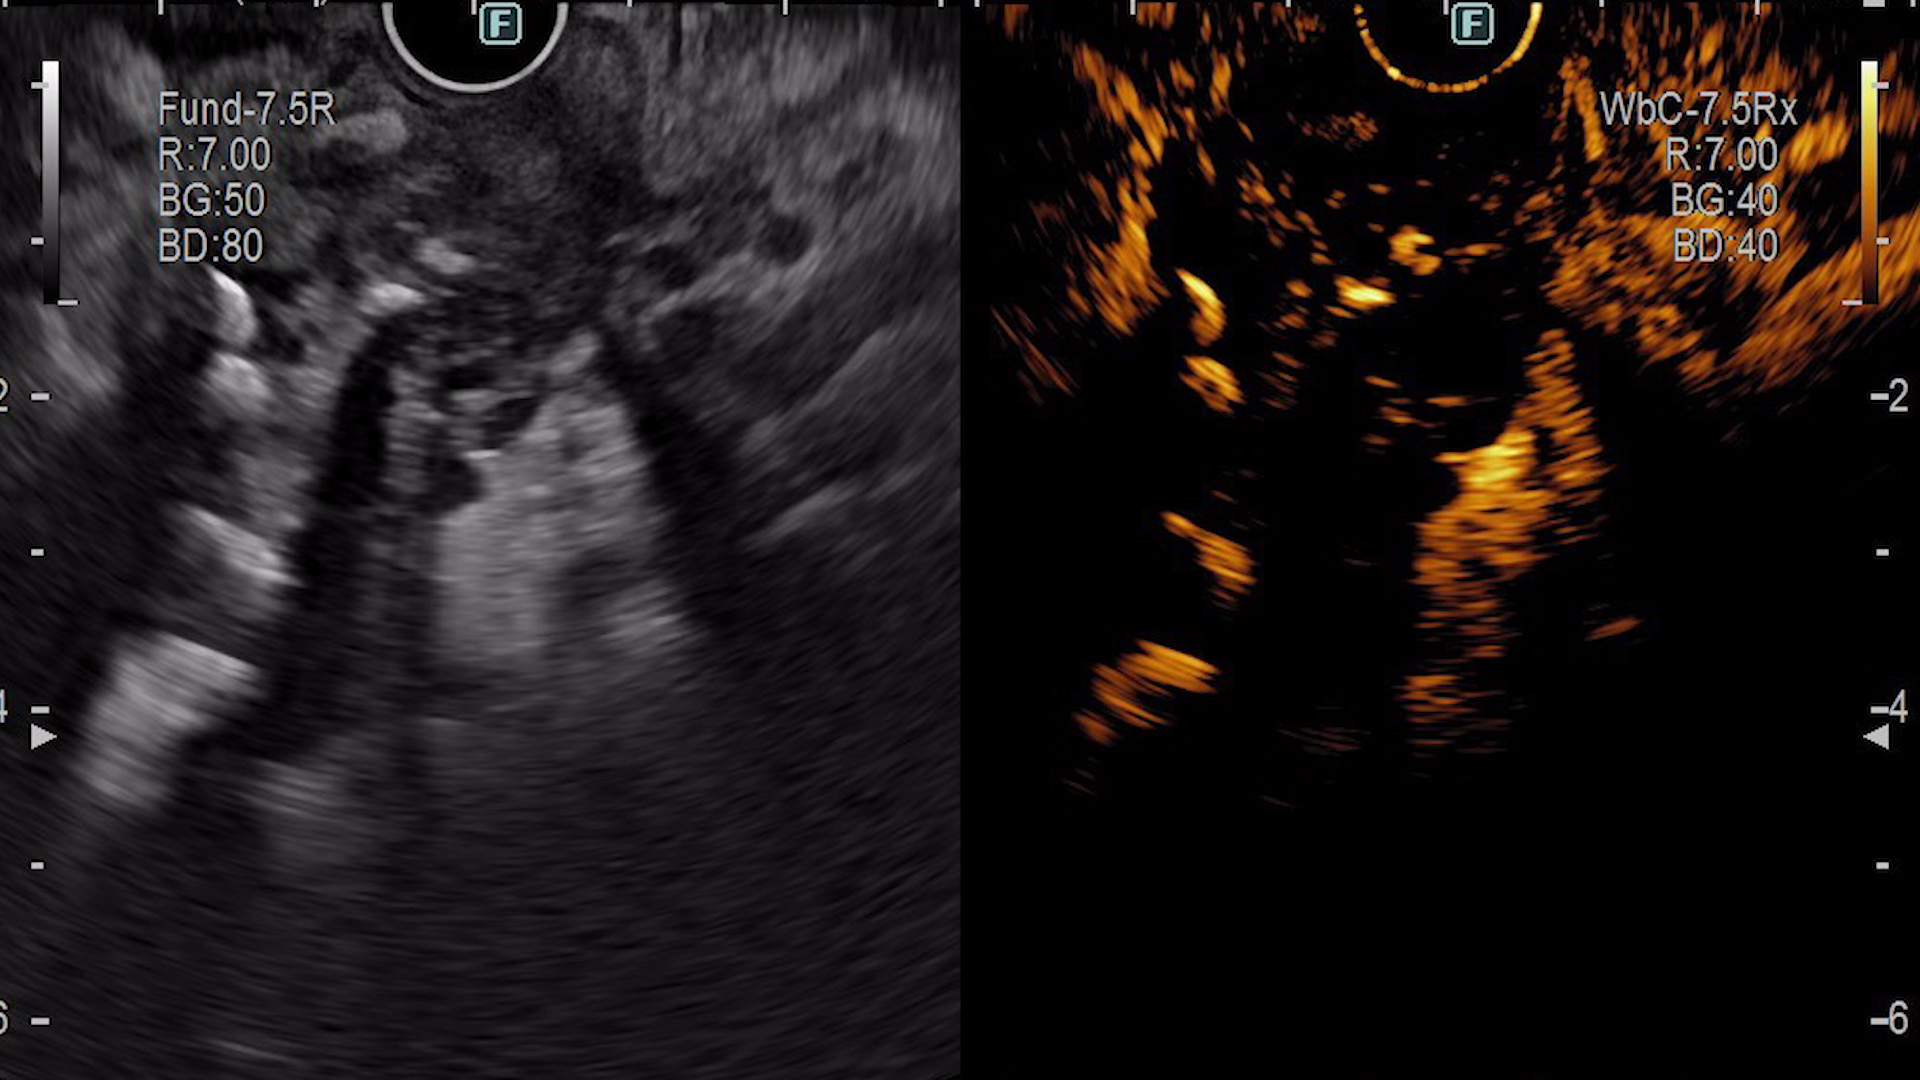

Ecoendoscopic (EUS) s-a evidențiat:

- Evaluarea ecoendoscopică:

- Modificări infiltrative ale parenchimului pancreatic cu extensie parietală gastrică și bulbară;

- Parenchim pancreatic global atrofic;

- Duct pancreatic principal dilatat difuz, cu traiect tortuos, conținând material ecogen sugestiv pentru mucină, precum și imagini hiperecogene cu con acustic posterior mobilizabile cu vârful acului de puncție, sugestive pentru mucină calcificată;

- Dilatarea ductelor pancreatice secundare.

- Ecoendoscopie cu substanță de contrast (CE-EUS):

După administrarea intravenoasă a 4,8 mL SonoVue, se identifică la nivel cefalopancreatic o zonă hipocaptantă, imprecis delimitată, cu ecostructură neomogenă, cu dimensiuni de aproximativ 40/26 mm. Leziunea a fost puncționată ecoendoscopic (EUS-FNB), efectuându-se două pasaje cu ac de 22G (Acquire, Boston Scientific).